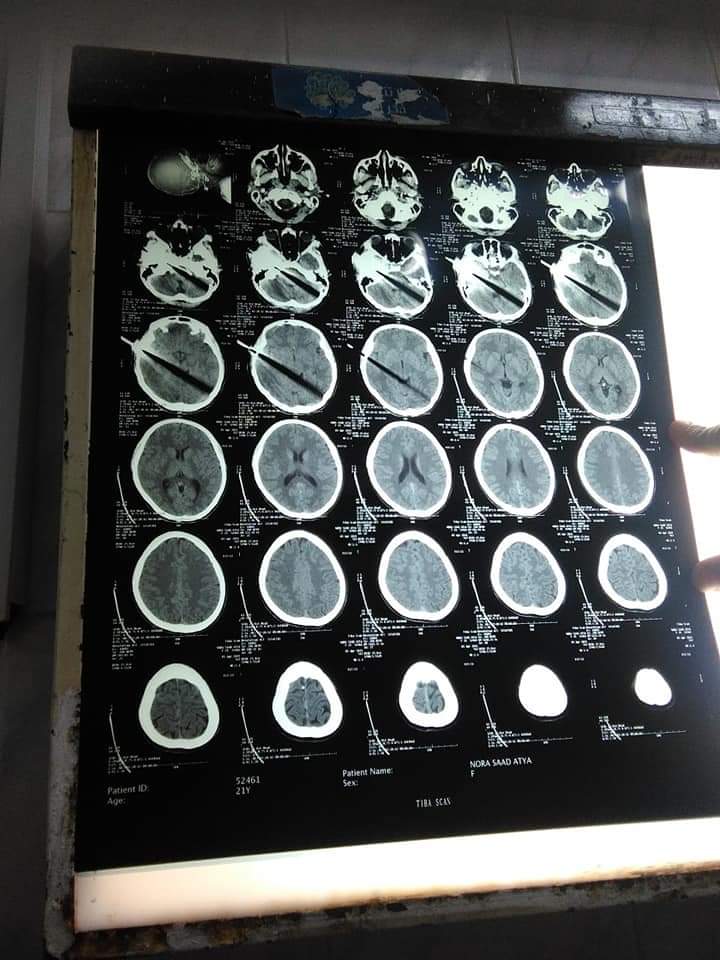

من جانبه، أكد الدكتور أحمد عزيز، رئيس جامعة سوهاج، أن المستشفى استقبل حالة "سيدة الساطور" بعد استمرار النزيف الدموي لها، إذ إنها كانت تعرضت للإصابة في الساعة الـ4 عصرًا، إلا أنها وصلت إلى المستشفى في وقت متأخر ليلًا.

وأضاف "عزيز"، أن الفريق الطبي بالمستشفى نجح في استخراج "ساطور" من جبهة سيدة، مؤكدًا أنها كانت في حالة سيئة جدًا وفاقدة للوعي، مشيرًا إلى أنه كانت مُصابة في جروح قطعية في الرأس وكسور في الجمجة، وأن كثيرًا من الأطباء تعاونوا في نجاح عملية السيدة، حيث إن أطباء الجراحة وأطباء المخ والأعصاب والوجه والفكين والجراحات الخاصة بالعيون شاركوا جميعًا في العملية، واستمرت لـ7 ساعات.

وأوضح عزيز أن الحالة مستقرة وفي وعي وتستجيب للعلاج وهناك تطور في حالتها، وتم عملية التجميل لتحسين حالة السيدة، متابعًا: "السيدة تعرضت للضرب بالساطور من ضرتها.. وتم اتخاذ إجراءات قانونية لمعاقبة المتهمة".